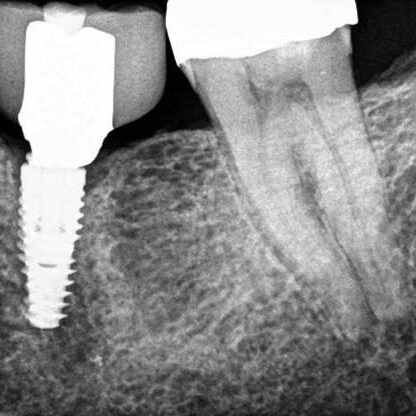

ULTRASONICS: Complications of Abutment Screw Retrieval Secondary to Prior Ultrasonic Attempts

There has been much written on the use of ultrasonics in retrieving fractured screw fragments, which I didn’t think a lot about until May of 2023, as it has not been a part of my fractured screw retrieval algorithm.